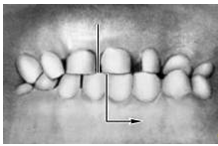

Прикус (occlusio) — соотношение зубных рядов при наиболее плотном смыкании зубов. Смыкание зубов верхней и нижней челюстей при различных движениях последней называется окклюзией. Откусывание и прожевывание пищи сопровождаются различными видами окклюзий. Откусывание осуществляется при передней (сагиттальной) окклюзии, когда смыкаются передние зубы, а боковые разобщаются (между ними появляется просвет). При жевательных движениях возникают боковые (трансверзальные) правая и левая окклюзии. Исходным и заключительным положением для всех жевательных движений нижней челюсти являются центральная (вертикальная) окклюзия, при которой линия, проходящая между центральными резцами обоих зубных рядов, совпадает со срединной линией лица.

Кроме аномалий П. в сагиттальной плоскости существуют аномалии П. в вертикальной и трансверзальной плоскостях. К основным вертикальным аномалиям (определяются по отношению к горизонтальной плоскости) относится открытый и глубокий П. Открытый П. (рис. 7, а) — наличие щели между зубными рядами при их смыкании, чаще в области передних зубов, реже в области боковых. Иногда смыкаются только последние моляры, что приводит к выраженным нарушениям жевательной функции и особенно речи. При глубоком П. (рис. 7, б) передние зубы одной из челюстей в значительной степени перекрывают коронки зубов-антагонистов, нижние резцы не опираются на зубные бугорки верхних резцов, а соскальзывают к их десневому краю, что приводит к постоянному травмированию десен и неба; нижняя часть лица укорочена за счет уменьшения или дистального положения подбородка.

Рис. 7а). Схематическое изображение челюстей при открытом прикусе.